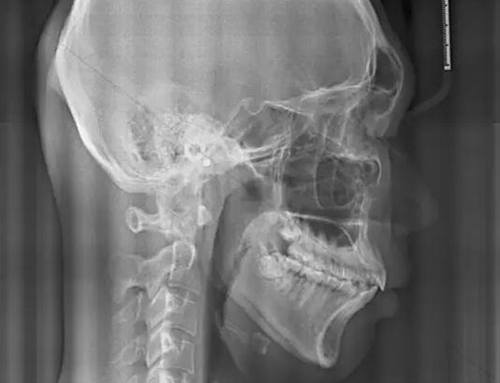

我們再來看兩張肥大的扁桃體

2.jpg